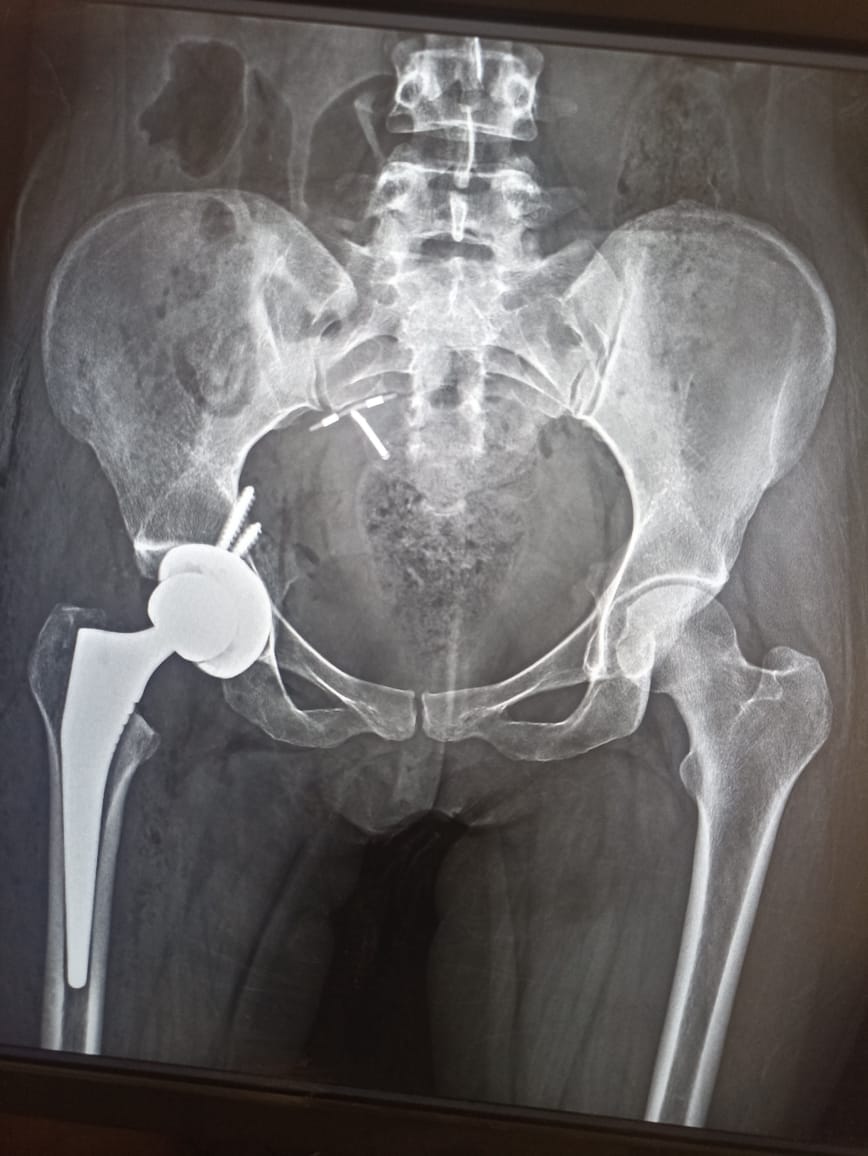

نجح فريق طبي بوحدة المفاصل الصناعية بمستشفى الإصابات بجامعة أسيوط في إجراء جراحة تغيير كامل لمفصل الفخذ بمفصل كامل صناعي لا اسمنتي عن طريق التدخل المحدود الأمامي للفخذ لمريضة تعاني من تآكل بمفصل الفخذ.

كان فريق طبي بوحدة المفاصل الصناعية قد استقبل فتاة تبلغ من العمر ٣٤ عاما، وتعاني من تآكل بمفصل الفخذ، والمعتاد في هذه الحالات أن تتم عملية التغيير عن طريق التدخل الجانبي ويتم خلالها قطع جزء من العضلات إلا الفريق الطبي قام بإجراء عملية جراحية شديدة الدقة للمريضة بدون قطع للعضلات، تجرى لأول مرة بصعيد مصر، من خلال فتحة صغيرة أمامية لا تتعدى ال ٥ سم، مما يتيح للمريضة العوده الوظيفية السريعة ويقلل من ضعف العضلات وحدوث العرج عقب الجراحة.

تشكل الفريق الطبي من قسم جراحة العظام من كل من الدكتور محمد كمال عبد الناصر أستاذ مساعد جراحة العظام، والدكتور محمد عنتر علي مدرس جراحة العظام بكلية الطب جامعة أسيوط.